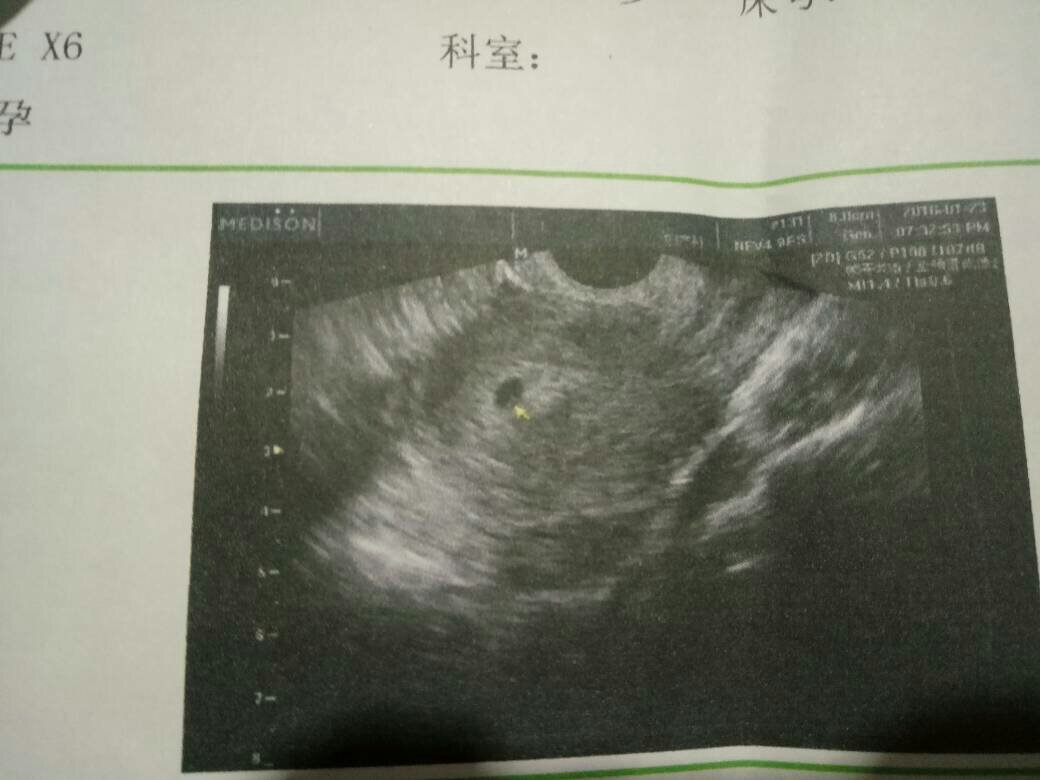

请问一下怎么辨别胎儿性别啊,有没有人能够看得懂这b超单子的啊,期待能够早一点知道是儿子还是女儿 请问一下怎么辨别胎儿性别啊,有没有人能够看得懂这b超单子的啊,期待能够早一点知道是儿子还是女儿 谢谢亲们了 点击展开 匿名用户 2016-01-30 15:19 为您推荐: 其他回答 至少3个月才能看 匿名用户 2016-01-30 15:41 给那医生塞几个红包你就知道了 匿名用户 2016-01-30 15:30 辨别男女 你就给5分奖励? 这么扣 匿名用户 2016-01-30 15:21 儿子 匿名用户 2016-01-30 15:21 相关问题 我想用b超单子辨别胎儿性别 有没有人可以帮我看看,我这张B超单子是否正常?我现在怀孕12周了??? 怀孕50天B超单子子宫前位6 1x5 8x5 0空腔2 1x1 7x0 9胎芽0 3 能知道胎儿性别吗?